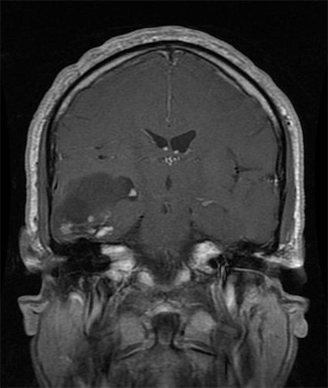

The patient is a 58-year-old woman who was diagnosed at an outside hospital with a World Health Organization (WHO) grade III non–contrast-enhancing right frontal anaplastic astrocytoma, with spread into the genu of the corpus callosum.